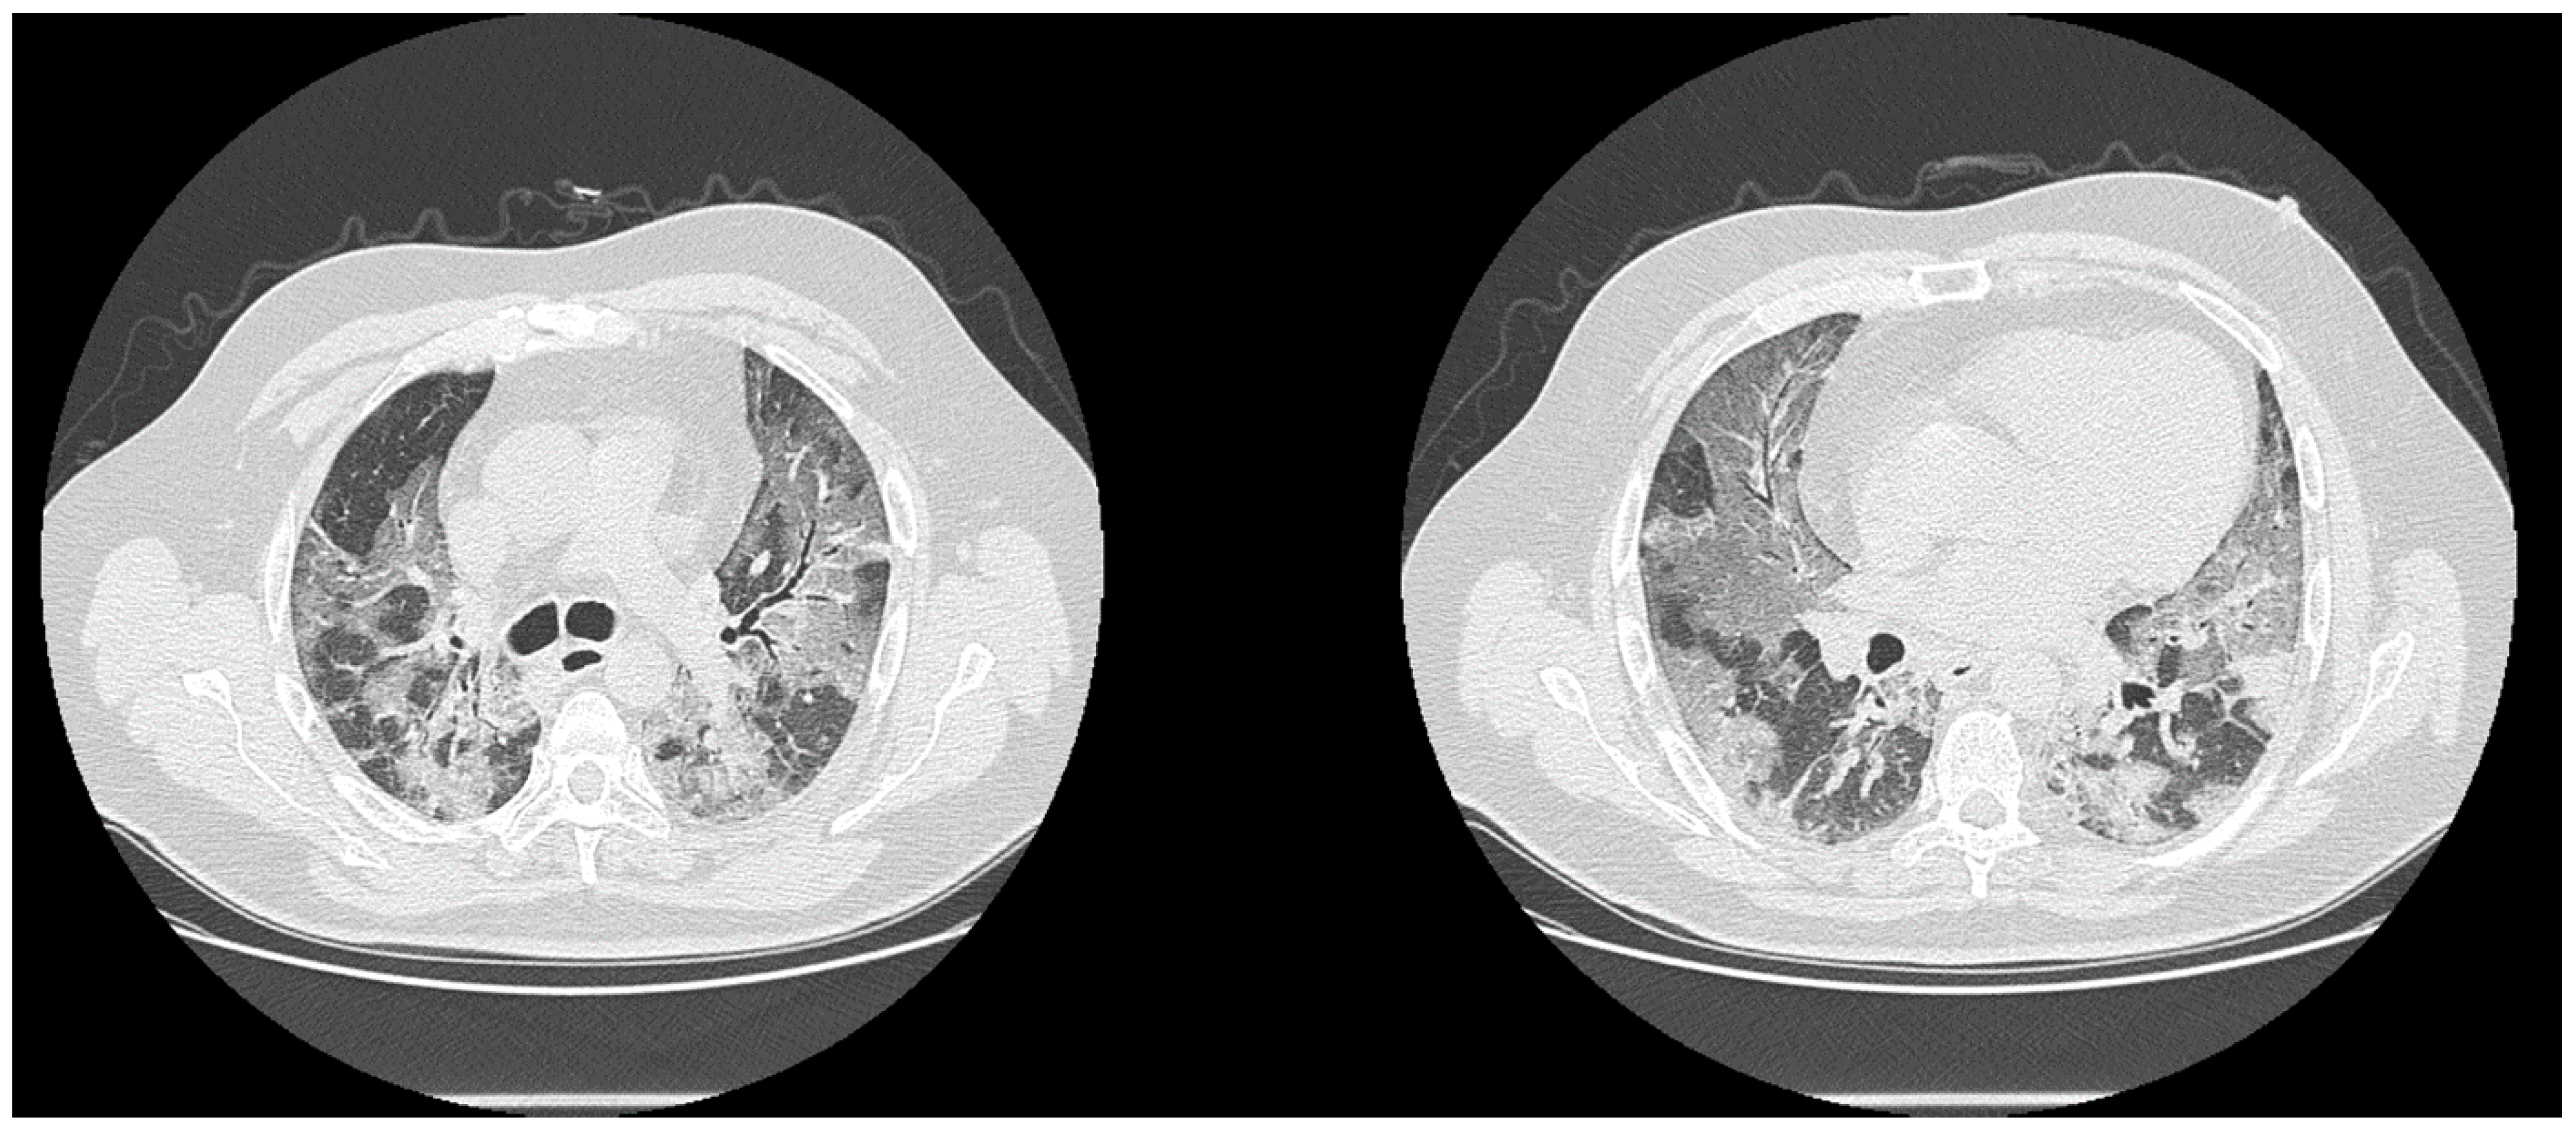

| High diagnostic confidence level | Bilateral multifocal GGO with predominantly peripheral distribution associated or not with septal thickening (crazy paving) and/or consolidations; multifocal GGO of rounded morphology associated or not with crazy paving and/or consolidations; multifocal GGO associated with findings of organizing pneumonia. |

| Intermediate diagnostic confidence level | GGO with diffuse distribution associated or not with crazy paving and/or consolidations; bilateral multifocal GGO and/or consolidations without a prevalent peripheral distribution and without rounded morphology; unilateral GGO with or without consolidation. |

| Low diagnostic confidence level | Isolated small areas of GGO and/or consolidations with non-rounded morphology were included in the low confidence level. |

| Negative for COVID-19 | Cases without the described alterations and with one or more of the following alterations were considered indicative of other diagnoses: isolated lobar or segmental consolidations, presence of solid or caveated nodules, presence of micro-nodules (centro-lobular micro-nodules and “tree in bud” pattern), smooth thickening of the interlobular septa with pleural effusion. |